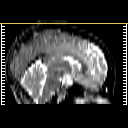

Metastatic bronchogenic carcinoma: T2-weighted MR -- Slice #23

[Home][Help][Clinical] Slice 23